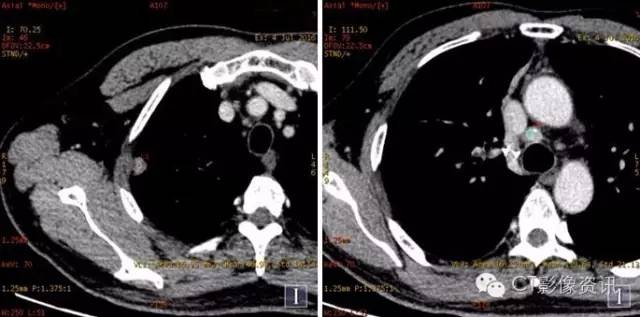

扫描方法 能谱平扫及两期增强扫描。病理已提示右上肺癌纵隔淋巴结转移;上腔静脉病灶为癌栓?血栓?左甲状腺病灶为转移?原发病灶? 常规平扫及静脉期

常规图像及碘基图均显示上腔静脉病灶明显强化。